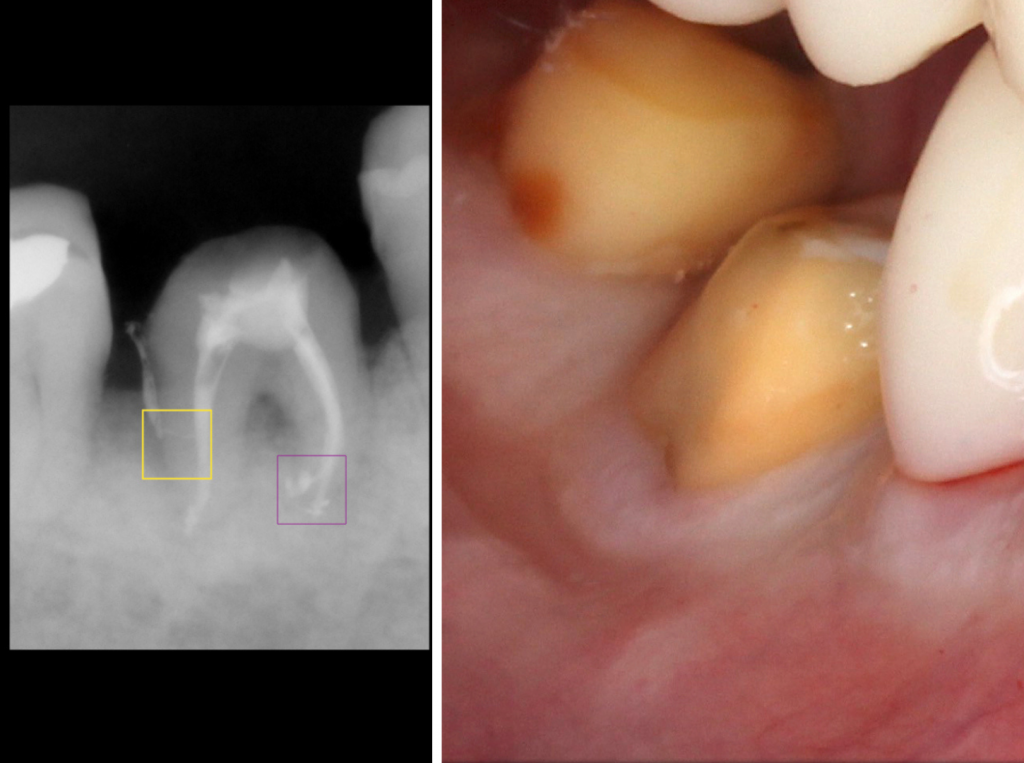

Es importante destacar que para obtener estos resultados es esencial utilizar magnificación en el tratamiento y llevar a cabo un aislamiento adecuado. Un especialista en endodoncia está capacitado para utilizar herramientas de alta tecnología para garantizar una mayor precisión y un mejor resultado en el tratamiento.

En nuestra clínica dental, contamos con especialistas altamente capacitados y con la última tecnología en endodoncia para garantizar un tratamiento de alta calidad y resultados impresionantes. Sabemos lo importante que es para ti conservar tus dientes naturales y estamos comprometidos a hacer todo lo posible para asegurarnos de que tengas una sonrisa sana y radiante.